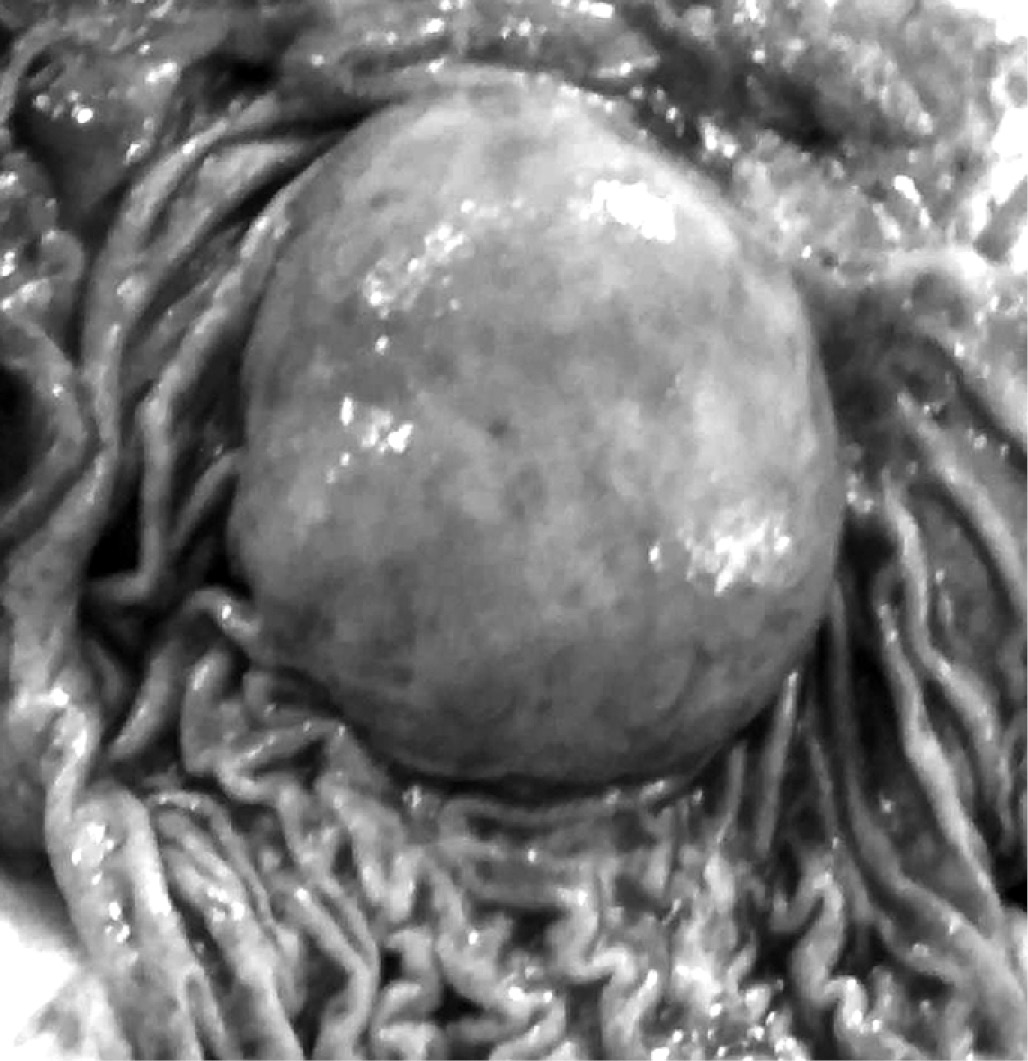

Макроскопическое описание удалённых анатомических структур: опухоль брюшной полости покрыта плотной капсулой, при пальпации – плотной консистенции, размерами 15×12×11 см (рис. 11), на разрезе – множественные кистозные полости и очаги некроза, заполненные темно-коричневым содержимым (рис. 12).

Рис. 11. Опухоль покрыта плотной капсулой, размерами 15×12×11 см